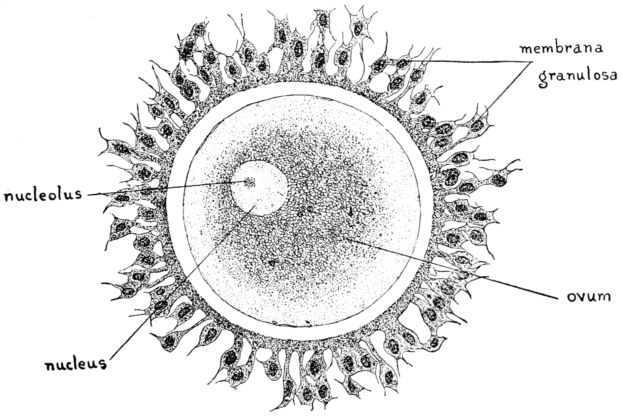

| 16. | Diagram of human ovum | 47 |

| 17. | Diagram of human spermatozoa | 61 |